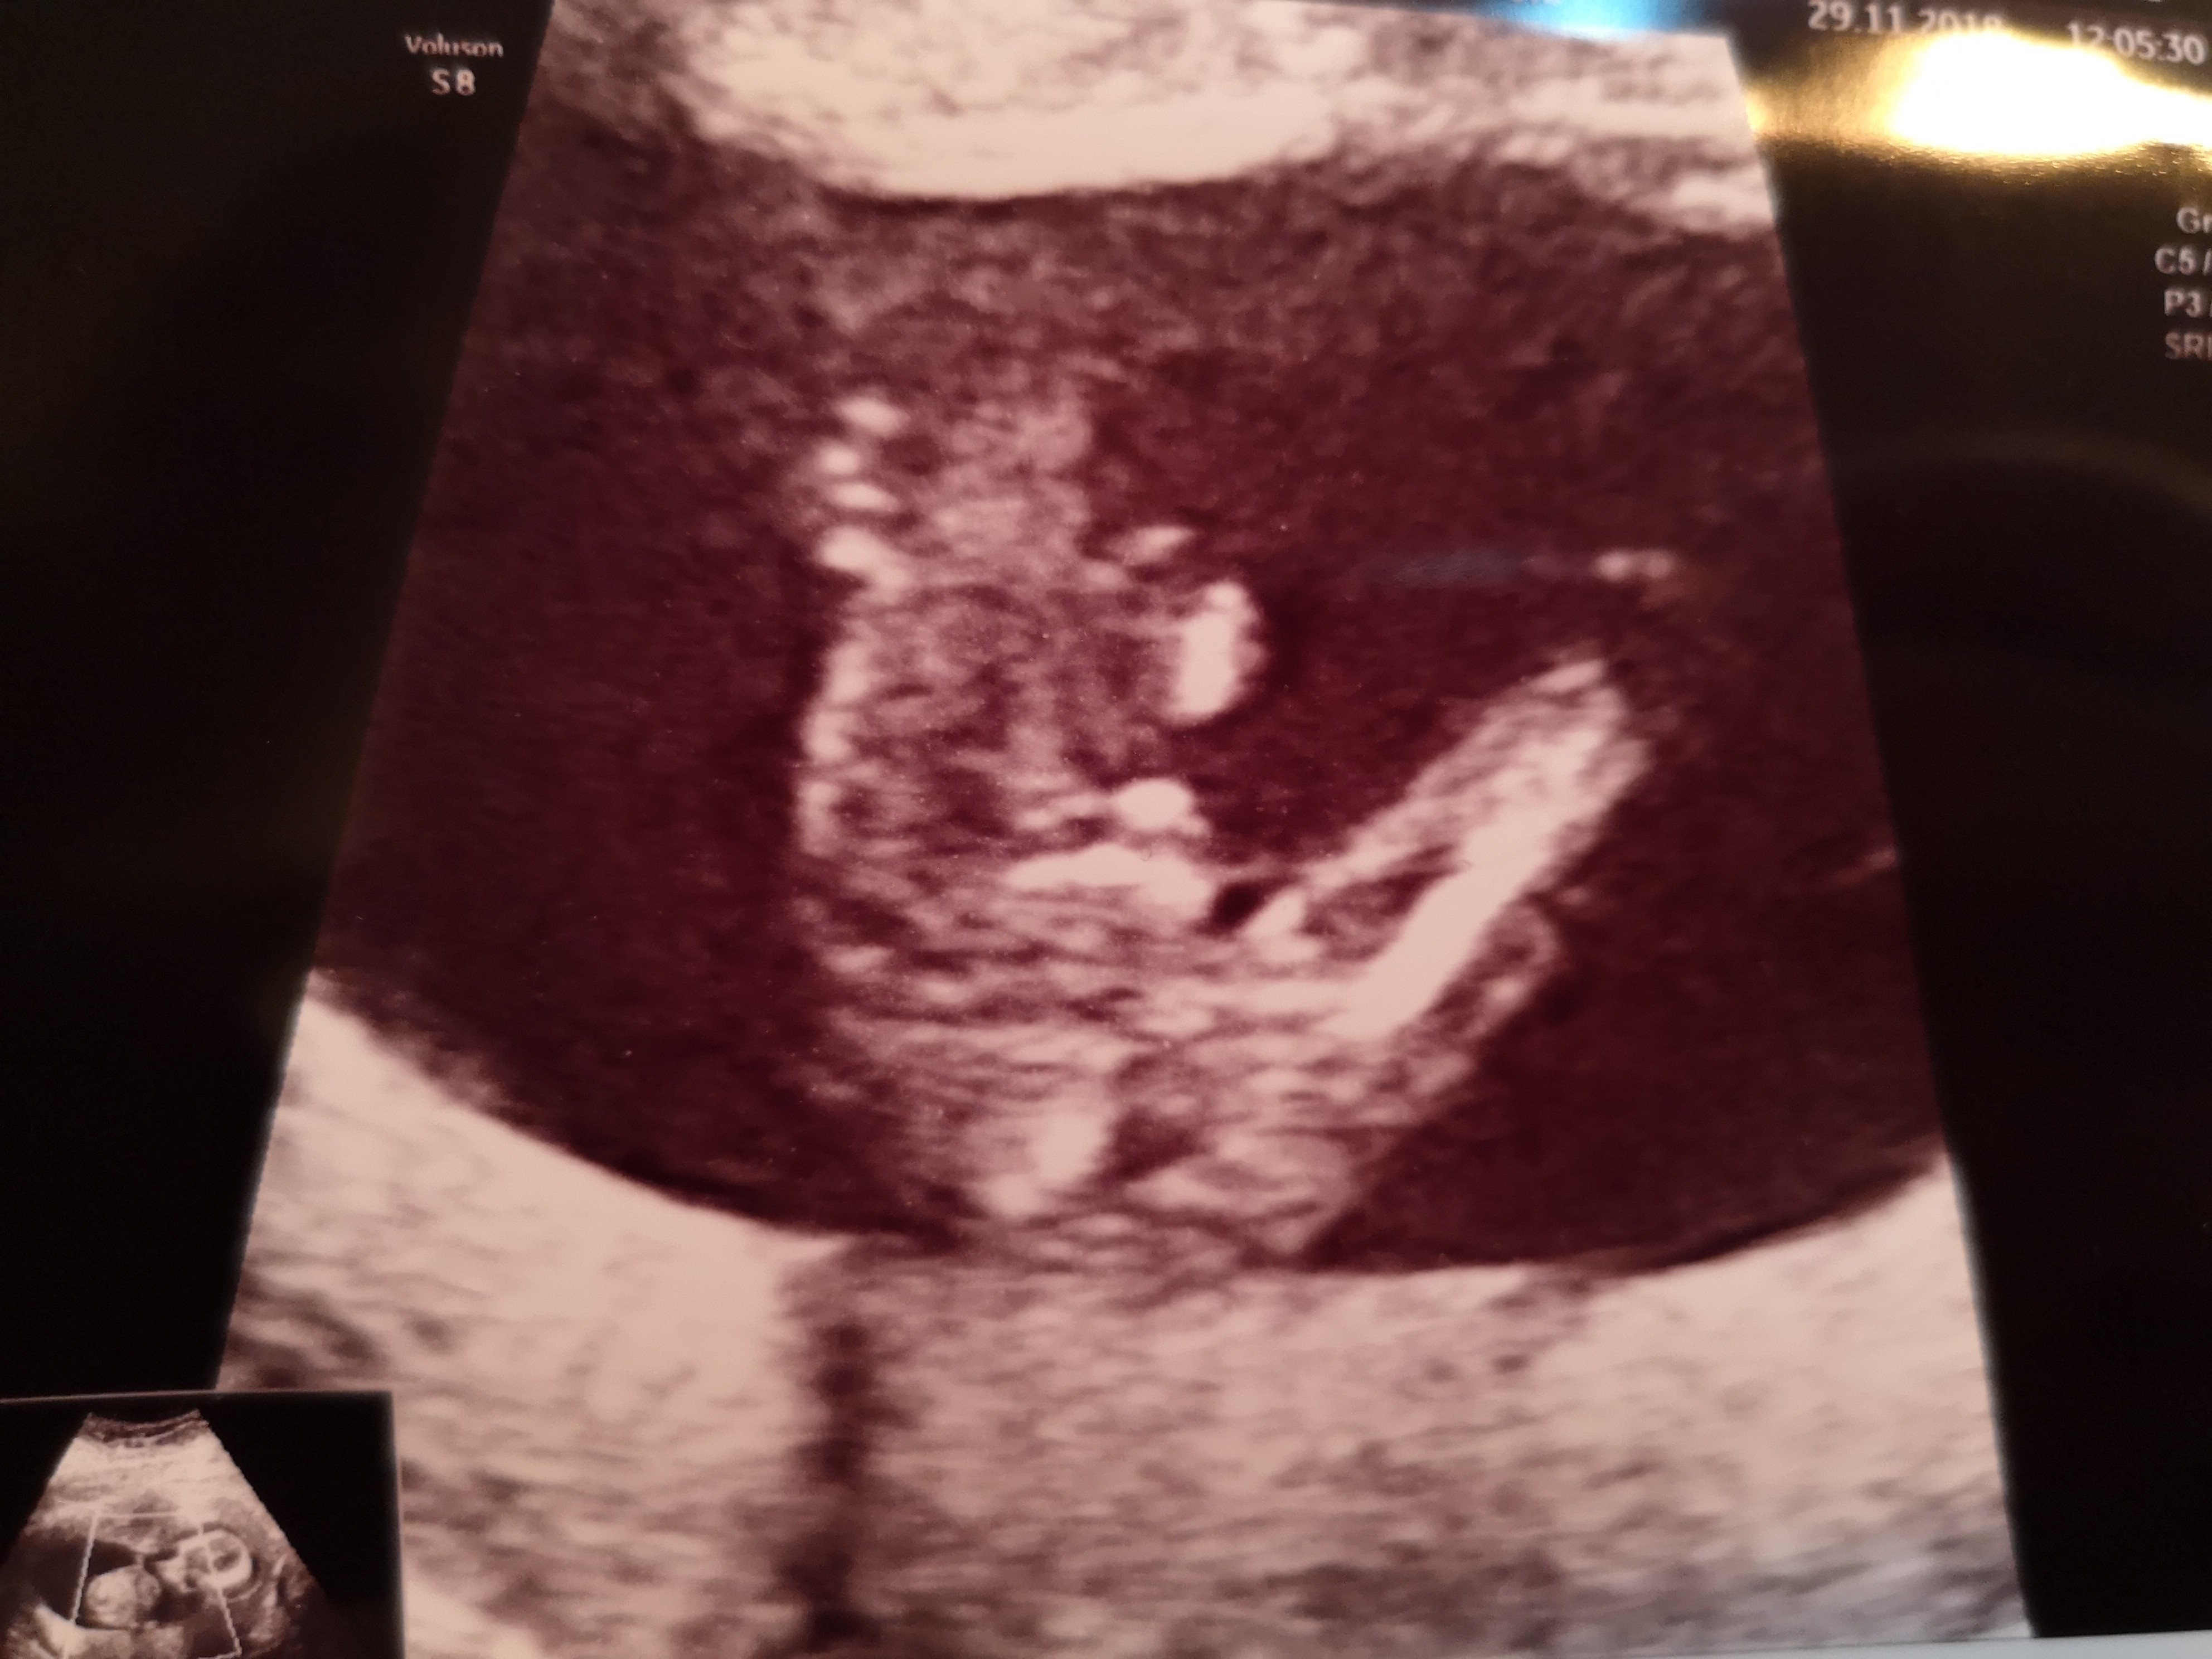

Cześć dziewczyny. Co sądzicie o moich zdjęciach? W 11tc5dc pierwsze zdj-lekarz stwierdził że na 75prc. dziewczynka. Tydzien później jeszcze raz byłam u niego, bo jeszcze musiał coś podejrzeć i w 12tc5d następne zdjęcia-powiedział że dziś na 75 prc. chłopak. Powiedział ogólnie że daje 50proc i trzeba poczekać do połówkowego. Czy ktoś miał tak szybką zmianę płci. Zdjęcia z obydwu badań wydają się jednoznaczne: na pierwszym dziewczynka, na drugim chłopiec. Czy już zostanie chłopiec?? Czy jest szansa że się zmieni? Ktoś tak miał? Dałybyście 100proc chłopak, czy jakąś nadzieję na dziewczynkę? Lekarz uznał, że jest jakiś procent kobiet u których się to zmienia, nie wiem co miał na myśli.

Załączniki

• IMG_20181129_084204.jpg

IMG_20181129_084204.jpg

1,5 MB · Wyświetleń: 2 680

• IMG_20181129_084349.jpg

IMG_20181129_084349.jpg

1,6 MB · Wyświetleń: 1 228

• IMG_20181129_084338.jpg

IMG_20181129_084338.jpg

1,5 MB · Wyświetleń: 1 234

• IMG_20181129_084140.jpg

IMG_20181129_084140.jpg

1,6 MB · Wyświetleń: 16 870

Za wczesnie lekarz ocenil plec pierwszym razem dlatego ze nub do 13 tc moze sie podniesc ...na poczatku wszystkie nuby sa dziewczynkowe.Raczej nastawialbym sie na chlopca ale poczekaj na polowkowe.